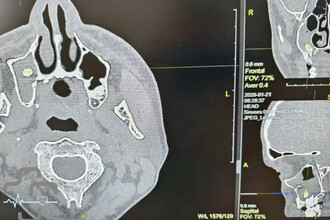

Россиянин едва не задохнулся из-за зуба в носу